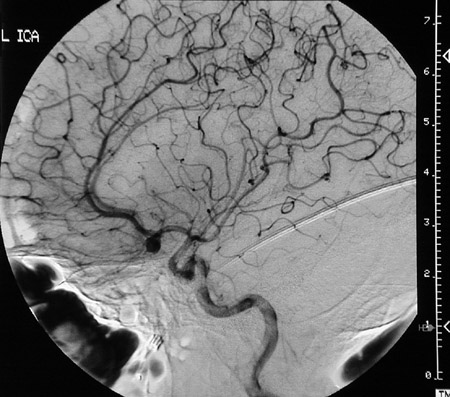

The cerebral angiogram above and below demonstrates a berry aneurysm involving the anterior communicating artery of the circle of Willis at the base of the brain.